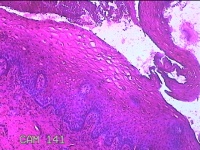

宫颈12点组织

性别

女

年龄

46岁

临床诊断

人乳头瘤病毒感染

一般病史

人乳头瘤病毒其他12高危型阳性

标本名称

大体所见

灰白暗红色组织0.8x0.5x0.2cm一块。